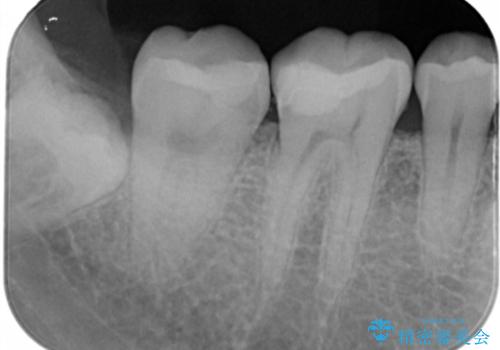

- 右下6・7番の治療のやり変えを主訴に来院された患者様です。

保険の材料が劣化し中で虫歯が進行しているため、古い材料と虫歯を全て除去した上で詰め直す必要がありました。

切削量・形態を考慮し、セラミックインレーでの治療を計画しました。

虫歯が深い場合、痛みなどの症状が出る可能性がありますが、経過は良好でご本人も満足されています。